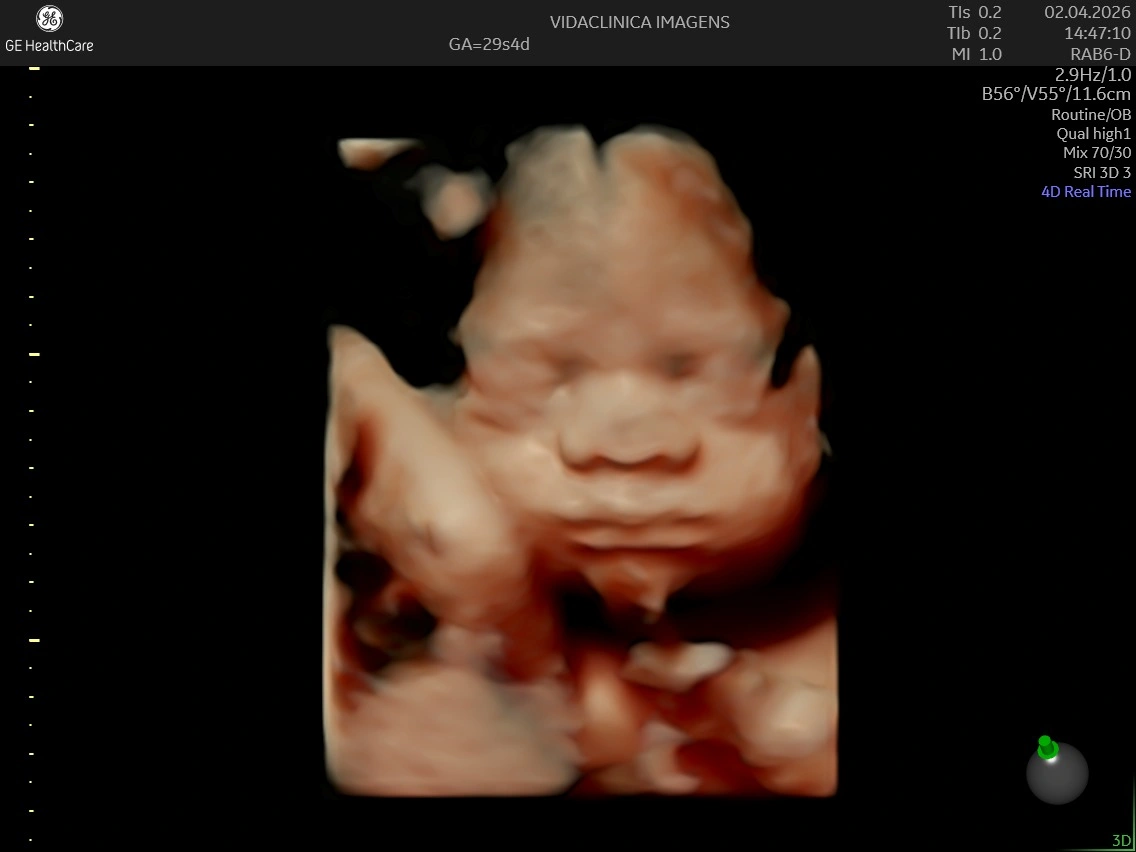

Acompanho detalhadamente toda a evolução do seu bebê ainda na sua barriga.

Realizo diversos tipos de ultrassonografia para garantir que seu bebê chegue ao mundo com saúde.

Estou pronta para realizar diagnósticos precisos sobre como anda a saúde do seu bebê ainda ai dentro da sua barriga. Realizo toda e qualquer tipo de ultrassonografia obstetríca.